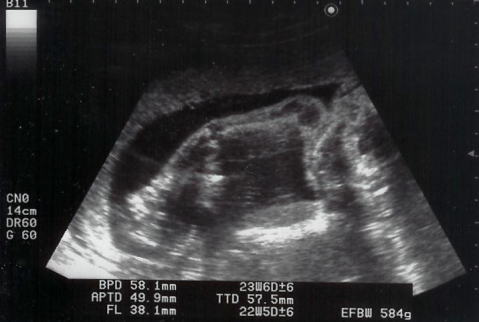

|  定期健診です。今日は二人ともお休みをいただきました。年末で病院は混んでいた上、ママは糖尿病の検査もあり半日かかりました。ママのお腹を見て、「急に大きくなったのね!」と看護師さん。shigeruはちょうどいい大きさだそうです。心臓は4つのお部屋、腎臓は2つありました。元気に動いていたけれど、今回はshigeruがうつ伏せになっていて、いいお顔が見えませんでした・・・性別は(まだ?)聞いていません。お薬3種類もらい、健診が終わりました。

うつ伏せに状態。右が頭。上方横に伸びるのが腕。